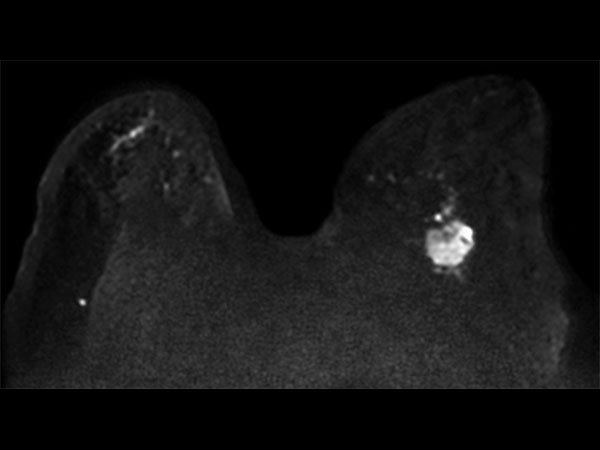

57 year old female with a new diagnosis of Ca. Sample obtained by US biopsy: Invasive Ductal Ca, grade 3. MR requested to aid in determining treatment.

Axial Diffusion (b800)